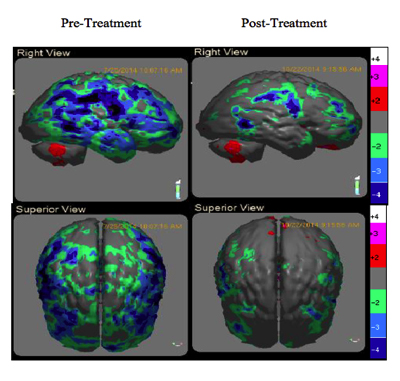

Uniquely, the proposed mechanism of PBM is the release of nitric oxide from cytochrome C-oxidase (COX) which increases ATP, genetic signalling to upregulate anti-inflammatory, local circulation, cell growth and protective factors. (7) (Fig 5) These processes promote improved brain function and subsequent clinical improvement. In a case series of 12 veterans with chronic mTBI lasting greater than 18 months, Hipskind et al demonstrated statistical improvements in cognitive function and rCBF using quantitative SPECT following PBMT. (Fig 7) This study used an FDA cleared InLight Medical PBM device (Fig 6) which pulsed both red (629nm) and near-infrared (850 nm) light transcranially for 20 minutes thrice per week for six weeks. Standard neuropsychological testing revealed improvements in 14 out of 15 subscales, with six of the 14 reaching statistical significance. In addition, quantitative brain SPECT imaging revealed improvements in rCBF in nine of 12 subjects. Subgroup statistical analysis of the nine with improved rCBF revealed quantitative blood flow improvements at the P<0.007 level. Although not formally evaluated, all subjects reported subjective improvements in mood, attention and sleep. There were no reported adverse effects.